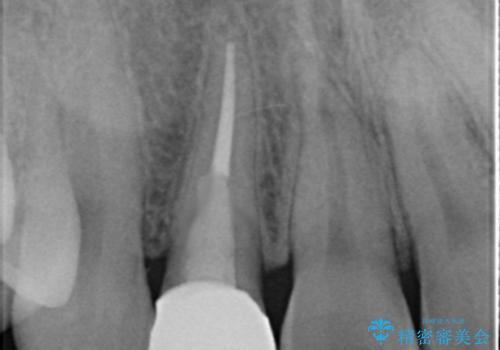

高校生の時に部活で前歯をぶつけて神経が死んでしまい、歯が黒く変色したためセラミッククラウンで治療したとのことでした。

精査したところ、透過性のあるセラミッククラウンで治療されており、内側の黒い土台が透けてクラウンが黒ずんで見えていました。

土台を白いファイバーコアにやりかえたのち、土台の色を透過させないジルコニアフレームを用いたセラミッククラウンによる治療を行いました。

失活(神経が死んでしまっていること)により黒くなった歯根が透けて歯ぐきも黒ずんで見えるため、歯肉移植の手術も提案しましたが、そこまでは気にならないとご希望されませんでした。